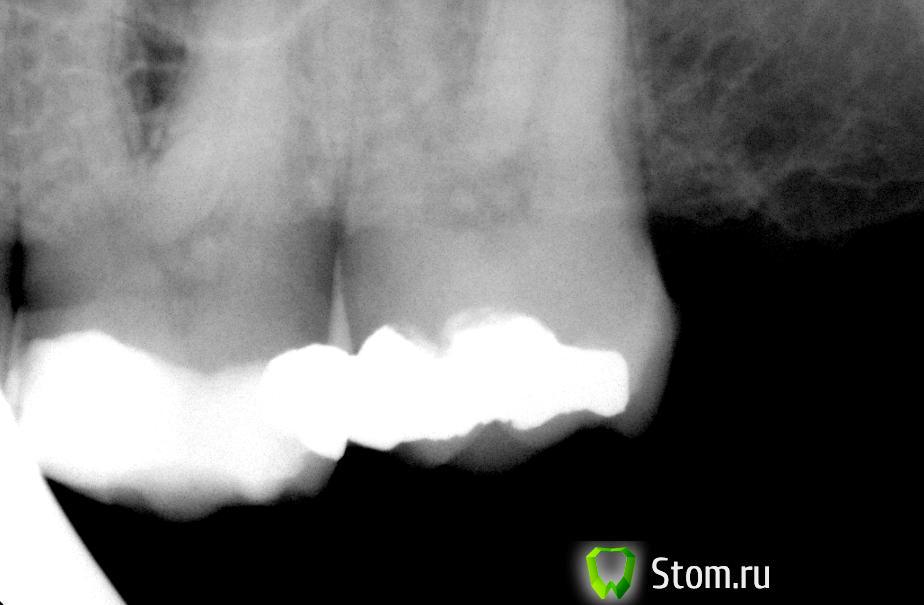

Ferny Опубликовано 27 февраля, 2012 Поделиться Опубликовано 27 февраля, 2012 Всем добрый день! Дайте пожалуйста ваши советы насчёт лечения зуба. Пациент 45 лет, зуб 26. Жалоба: когда кусает твёрдую пищу типа сухарей и попадает на 26 зуб то начинается боль, довольно острая, которая проходит в течение двух минут. Просто так зуб не болит. Перкуссия и пальпация безболезненная. Пломбу ставили по словам пациента очень давно, но боль появилась только месяц назад примерно. На рентгене большая пломба, но вроде не достаёт до пульпы. Коллеги на работе посоветовали депульпировать. на 27 зубе амальгама. Не знаю что делать с зубом. Сразу депульпировать ...или...ещё что то предпринять? Что Вы можете посоветовать? Спасибо! Ссылка на комментарий

Ferny Опубликовано 27 февраля, 2012 Автор Поделиться Опубликовано 27 февраля, 2012 дистально я высверлила пломбу и кариеса там не было...высверлила так же мезиально на 27. тоже ничего не было. поставила временные пломбы. когда я начала дистально высверливать то обнаружилось что под композитом была амальгама. я и её высверлила но под ней так же ничего не было. Вот после этого и не знаю что дальше делать. в пятницу придёт обратно Ссылка на комментарий